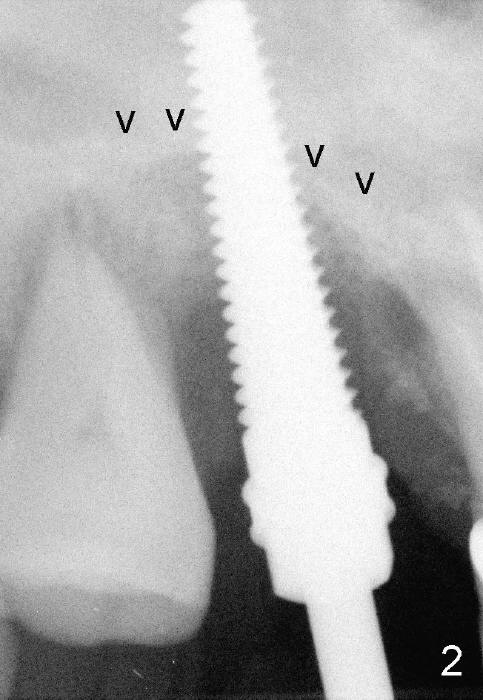

The 60-year-old man is a bruxer. All of the three upper right molars are nonsalvageable (Fig.1). Since #2 is symptomatic, it is planned to be extracted and restored first. As expected, there is severe alveolar destruction (single large socket), while the base bone is solid. A series of tapered osteotomes (2-5 mm) are used to create osteotomy in the base bone (gaining 4 mm into new bone), followed by 4.5x20 mm tap at the depth of 17 mm from the gingival margin (Fig.2). Then the depth is adjusted to 14 mm; the bone expansion and osteotomy continue until using 7 mm tap with good binding to the bone (Fig.3). A 7x14 mm implant is placed with insertion torque more than 60 Ncm (Fig.4). No bone graft is used for sinus lift considering sinus membrane perforation. The buccal flap is raised to reveal bony defect, which is covered by Osteogen (a synthetic bone graft) and then collagen membrane (Fig.6 *). Five days postop, the membrane undergoes a type of transformation (Fig.7 *) leading to a gingival tissue (Fig.8 *, 18 days postop). By 3 months, the gingiva has normal appearance (Fig.9), while the implant seems to be osteointegrated (Fig.10). Once the infected source is removed, our body has potential to regenerate.